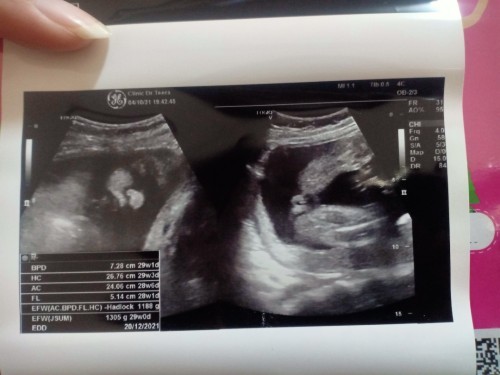

28 ธันวา ลูกสาวค่ะ👧🏻❤️